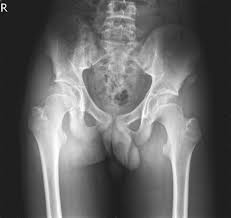

What is pelvis avulsion fracture?1. An avulsion fracture occurs when a tendon or ligament attached to a bone pulls against it and fractures off a piece of the bone. A pelvic fracture is a disruption of the bony structures of the pelvis. Your doctor might recommend that you use crutches to keep weight off the hip while it heals. A pelvic avulsion fracture is where the tendon comes away from the bone, often taking a piece of bone with it.

Pelvic Avulsion Fracture Symptoms Causes And Treatment from www.sportsinjuryclinic.net In the pelvis, the newly formed secondary centers of ossification, the apophyses, are the most likely portions of the bone to avulse. In adults, the ligaments and tendons tend to be injured first, whereas in children the bone may fail before. Physical therapy may also help a fracture heal more quickly than immobilization alone. Pelvis injuries range from the benign to life threatening. Your doctor might recommend that you use crutches to keep weight off the hip while it heals. Avulsion fractures are more common in children than in adults. Your doctor might recommend that you use crutches to keep weight off the hip while it heals. Aiis and ischial tuberosity fractures are at increased risk of developing future pain and nonunions, respectively.

Pelvic avulsion fractures are usually caused by activities or sports that need speed and sudden stops. Though more common in children, athletic adults are also prone to avulsion fractures. Other sites in the upper extremity involve the humerus and include the greater and. A pelvic avulsion fracture is where the tendon comes away from the bone, often taking a piece of bone with it. Avulsion fractures are caused by trauma. Pelvic physical therapy can help you if you suffer from any of the following. They include pelvic ring fractures [significance of physical examination and radiography of the pelvis during treatment in the shock. In adults, the ligaments and tendons tend to be injured first, whereas in children the bone may fail before. Apophyseal avulsion fractures are usually the result of a sudden forceful concentric or eccentric contraction of the muscle attached to the apophysis. Physical exam should not be used to rule out a pelvic fracture in unconscious patients, but it can nearly definitively rule it in. They usually happen when a bone is moving one way, and a tendon or ligament is suddenly pulled the opposite way. Patients and families need to be counseled about this. Many hip fractures can be treated with physical therapy, rest, or injections.